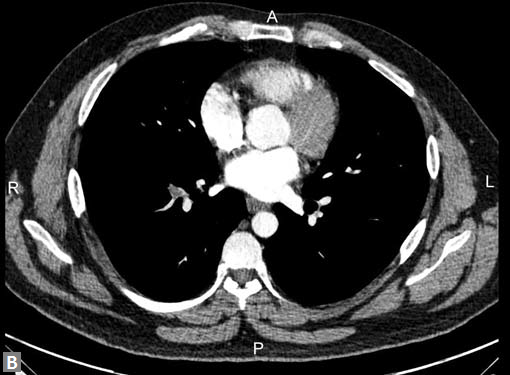

Filling defects (Figs 16A and B) may be seen in main

pulmonary artery (MPA), left pulmonary artery (LPA) and

right pulmonary artery (RPA), interlobar artery, segmental

divisions (Figs 17A and B). On occasions, detection in distal

parts of segmental divisions is difficult. This can be further

confounded by motion artifacts, non- or minimally opacified

accompanying pulmonary veins.